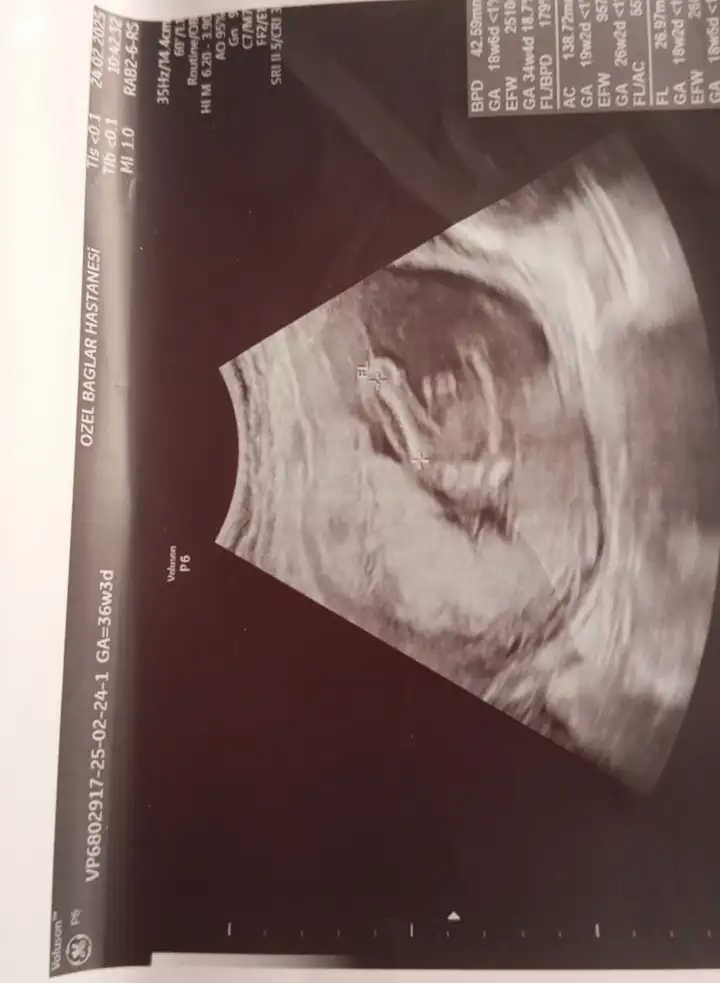

Bunada bakar mısınız rica edersemkız gibi

Bunada bakar mısınız

Bunlarada bakabilir misiniz

bacak arası görüntü anlamıyorum canımBunlarada bakabilir misiniz